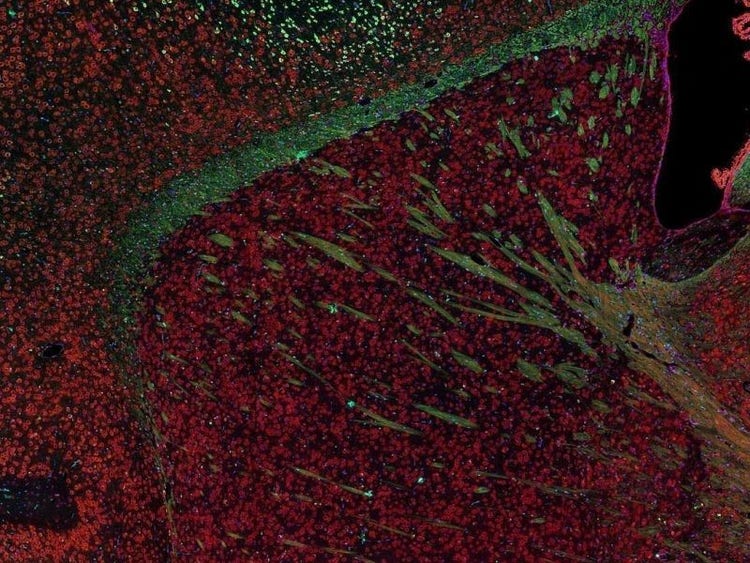

Fluorescence imaging of a mouse brain

Jedes dieser Bilder sieht aus der Nähe anders aus, aber sie fügen sich zu einem Bild eines Mäusegehirns zusammen, das mit Fluoreszenzbildgebung aufgenommen wurde.

Der britische Wissenschaftler Sir George G. Stokes beobachtete zum ersten Mal, dass das Mineral Flussspat fluoresziert, wenn es mit ultraviolettem Licht beleuchtet wird, und prägte den Begriff „Fluoreszenz“. Stokes fand heraus, dass das fluoreszierende Licht eine größere Wellenlänge hat als das Anregungslicht, ein Phänomen, das heute als Stokes-Verschiebung bekannt ist. Die Fluoreszenzmikroskopie ist eine hervorragende Methode zur Untersuchung von Materialien, die entweder in ihrer natürlichen Form (Primär- oder Autofluoreszenz) oder nach Behandlung mit fluoreszierenden Chemikalien (Sekundärfluoreszenz) fluoreszieren können.